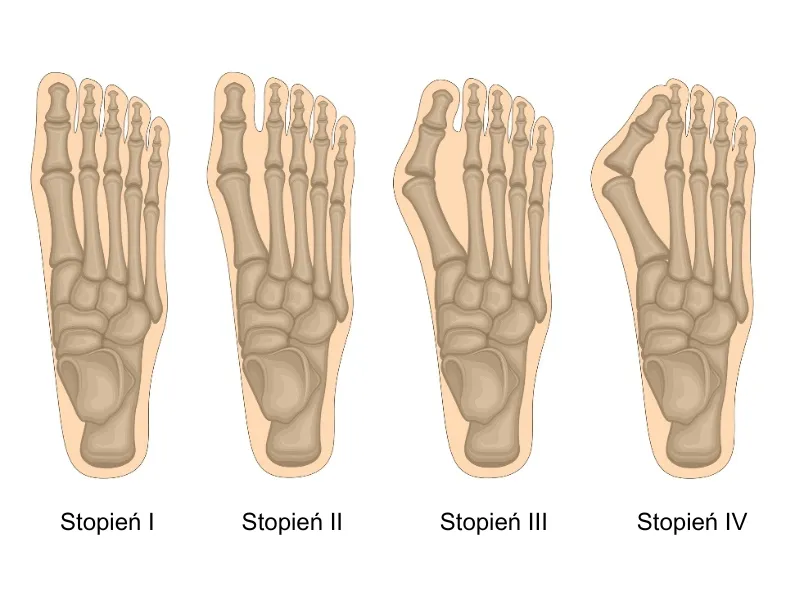

Analiza kątów deformacji: co lekarz widzi na zdjęciu rentgenowskim?

Na zdjęciach rentgenowskich oceniam szereg parametrów, które są kluczowe dla postawienia diagnozy i wyboru metody operacyjnej. Najważniejsze z nich to kąt koślawości palucha (HVA hallux valgus angle) oraz kąt międzypalcowy (IMA intermetatarsal angle). HVA mierzy stopień odchylenia palucha od osi stopy, natomiast IMA wskazuje na rozchylenie pierwszej i drugiej kości śródstopia. Analiza tych kątów, w połączeniu z oceną stanu stawu śródstopno-paliczkowego i ewentualnych zmian zwyrodnieniowych, pozwala mi precyzyjnie dobrać technikę operacyjną, która będzie najbardziej efektywna w Twoim przypadku.

Współczesna ortopedia oferuje wiele zaawansowanych technik operacyjnych, które pozwalają na skuteczną korekcję haluksów. Wybór metody zależy od stopnia deformacji i indywidualnych potrzeb pacjenta. Oto najpopularniejsze z nich:

Wybór metody operacyjnej nigdy nie jest przypadkowy. Zawsze jest to indywidualna decyzja, którą podejmuję wspólnie z pacjentem, po dokładnej analizie wszystkich czynników. Decydujący wpływ mają: stopień deformacji (oceniany na RTG), stan stawów, wiek pacjenta, jego poziom aktywności fizycznej oraz ogólny stan zdrowia. Na podstawie tych danych oraz oceny kątów HVA i IMA na zdjęciach rentgenowskich, jestem w stanie zaproponować najbardziej odpowiednią i skuteczną technikę, która zapewni najlepsze i najtrwalsze rezultaty.